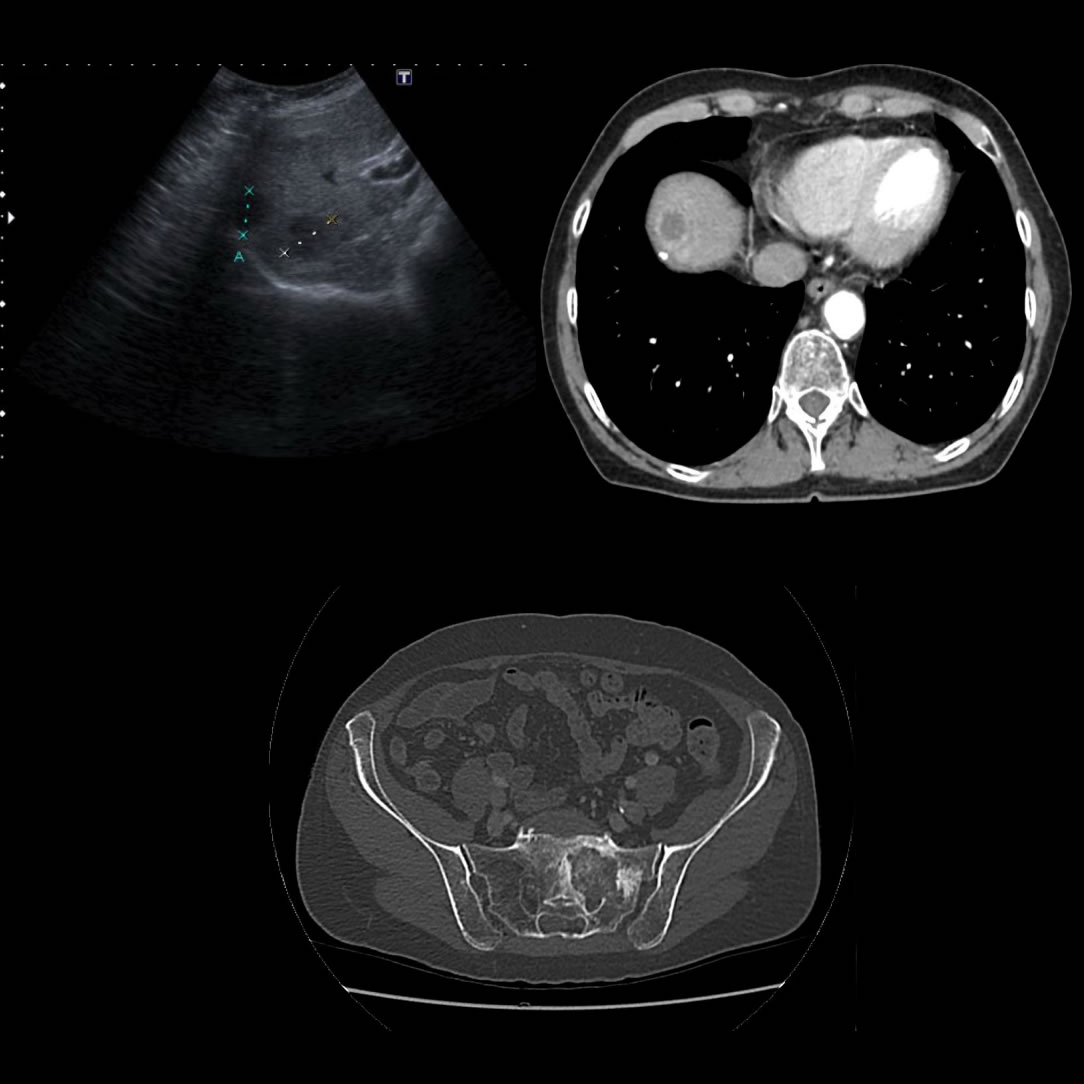

Femenina // 66 años

MC: Dolor Abdominal

● Dolor abdominal hipocondrio derecho y pérdida de peso

● Dolor a la palpación profunda en hemiabdomen derecho.

● Tx Hepático(2006)